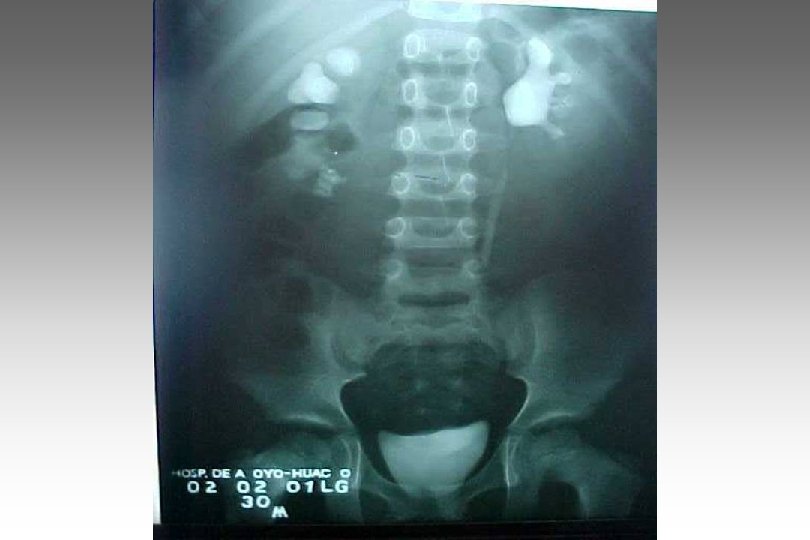

SECUENCIA DE IMAGEN o ECOGRAFIA. o CISTOURETROGRAFIA RETROGADA POST MICCIONAL. o PIELOGRAFIA ENDOVENOSA o GAMMAGRAFIA RENAL CON DMSA-TC 99. o RADIORENOGRAMA o UROGRAFIA POR RMN o TAC HELICOIDAL o ENDOSCOPIA VIRTUAL